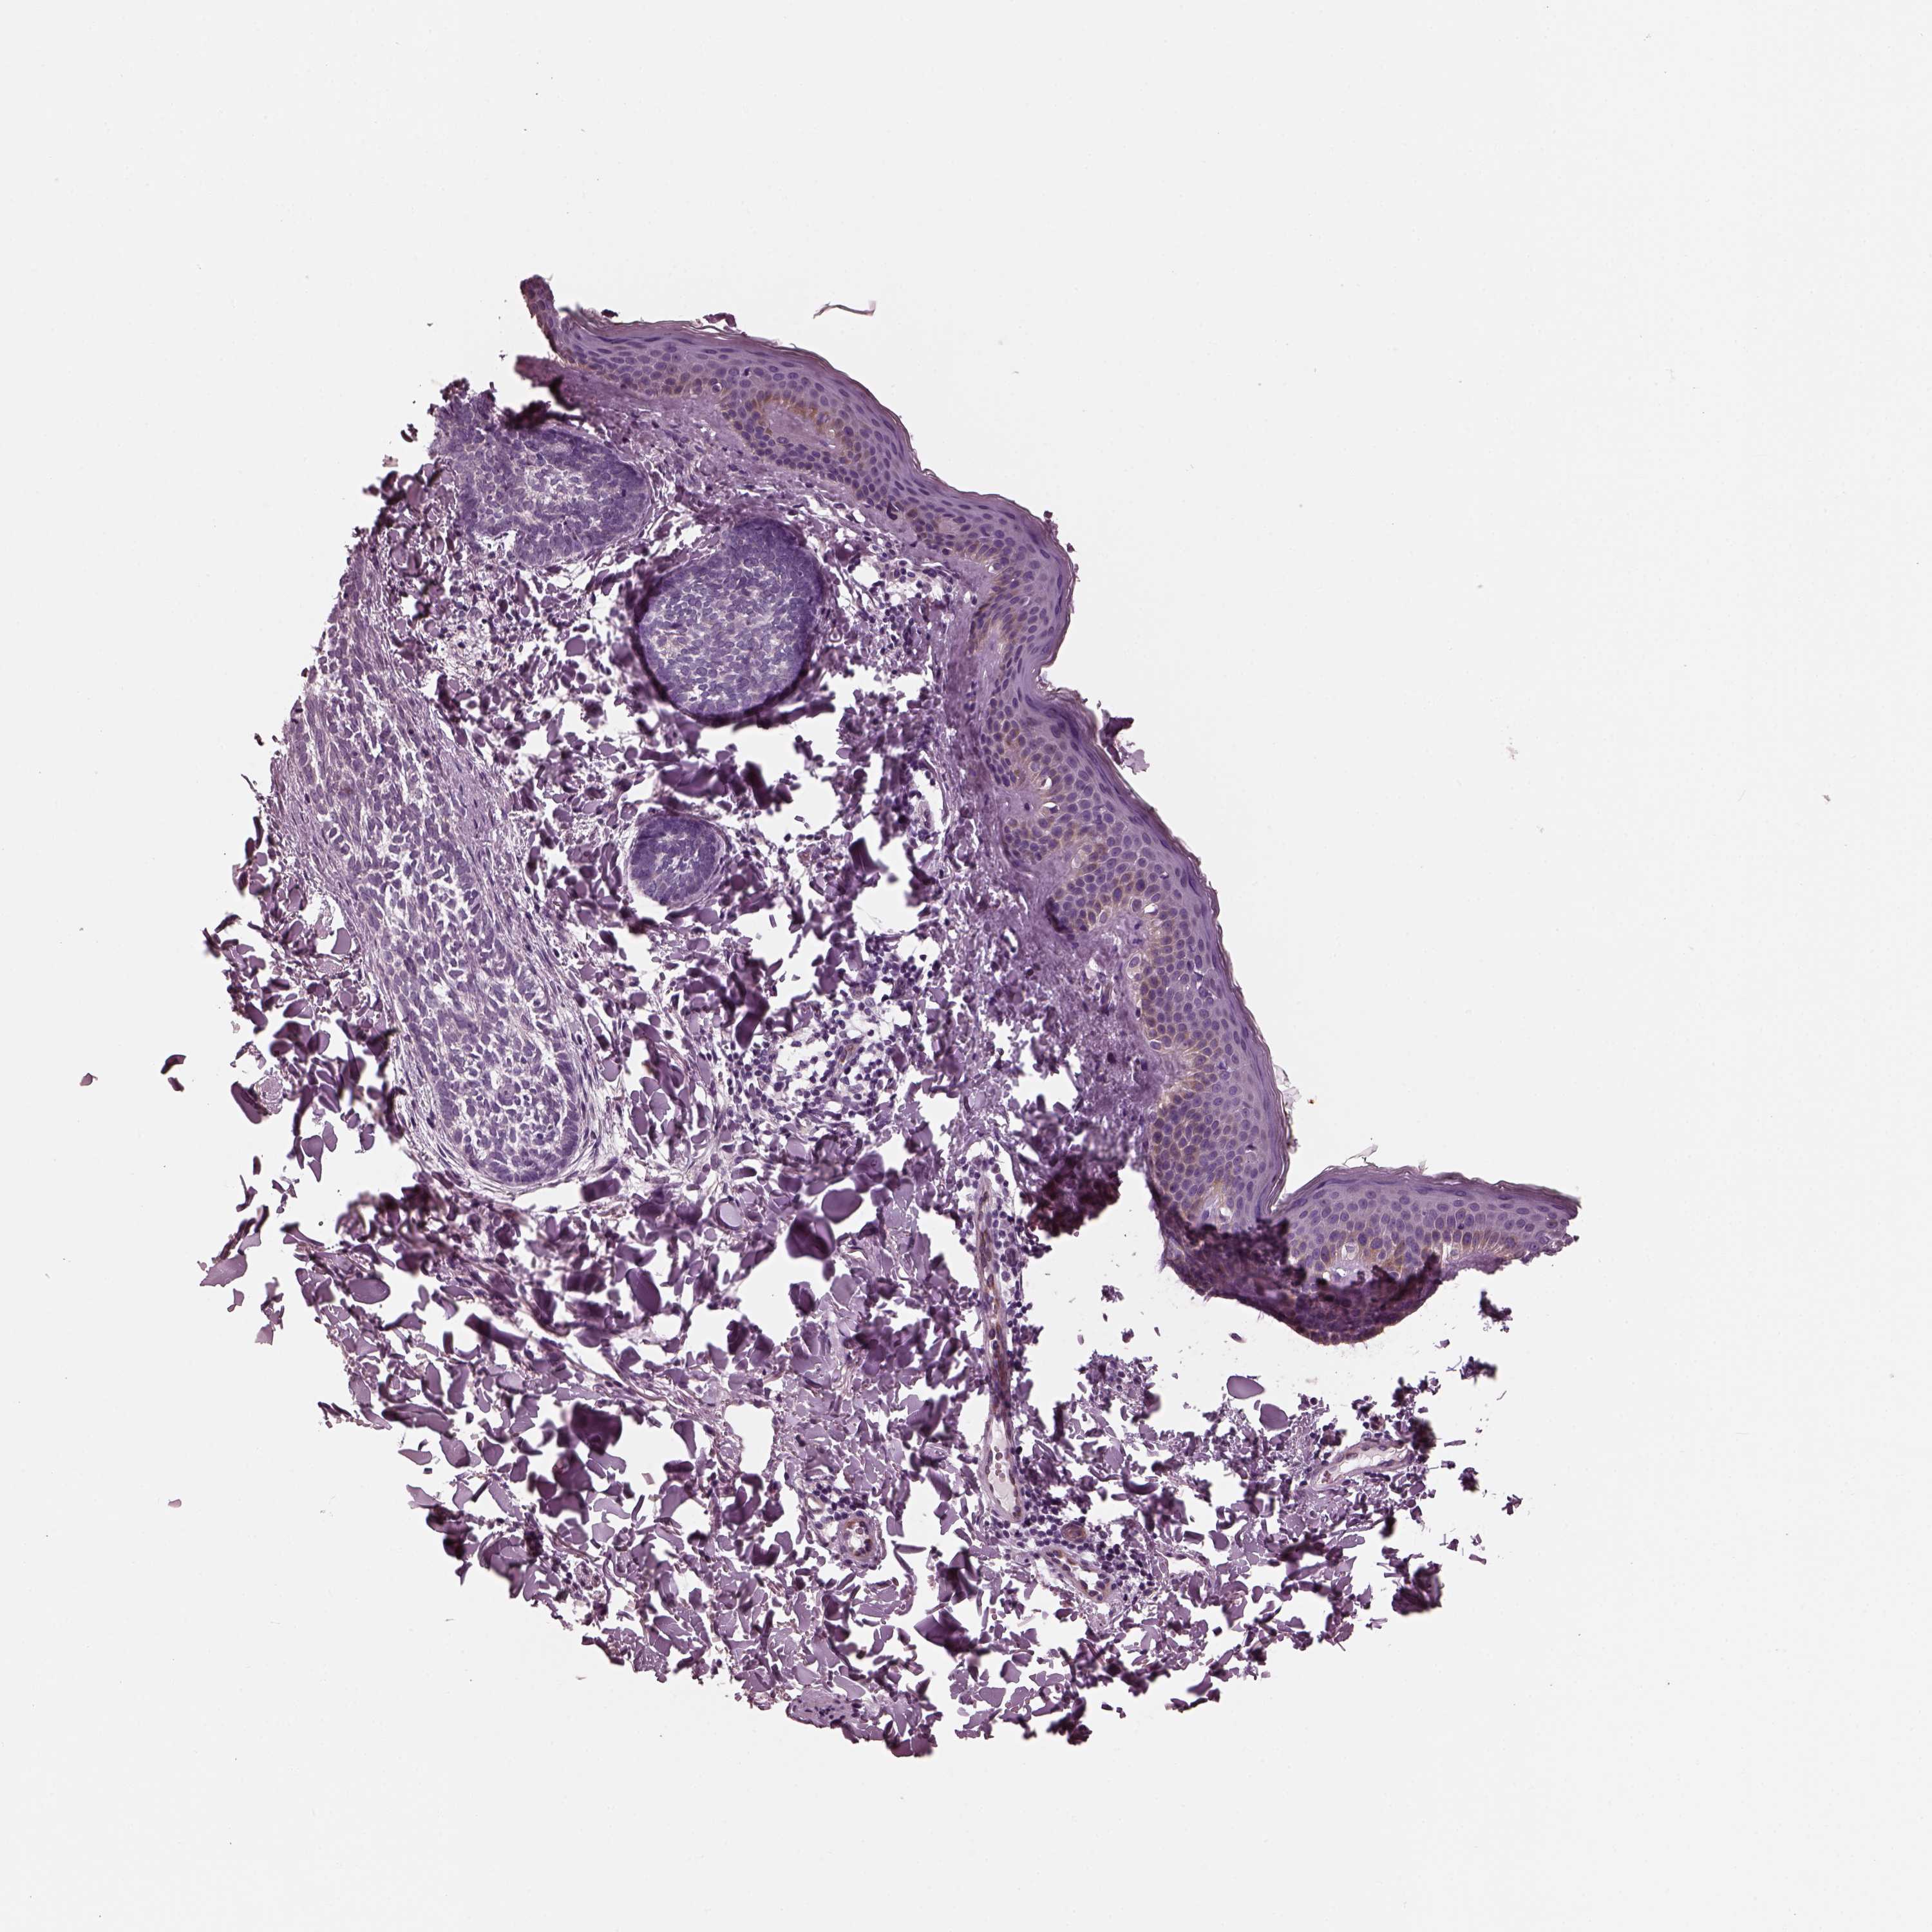

CANCER SKIN CANCER Show tissue menu

Basal cell and squamous cell cancer

SKIN CANCER - Protein expressioni

A mouse-over function shows sample information and annotation data. Click on an image to view it in a full screen mode. Samples can be filtered based on level of antibody staining by selecting one or several of the following categories: high, medium, low and not detected. The assay and annotation is described here.

Each image is clickable and will lead to virtual microscopy that enables deeper exploration of all samples and also displays staining intensity scores, fraction scores and subcellular localization as well as patient and tissue information for each sample.

Antibody HPA038811

Staining

High

Medium

Low

Not detected

Intensity

Strong

Moderate

Weak

Negative

Quantity

>75%

75%-25%

<25%

None

Location

Nuclear

Cytoplasmic/membranous

Cytoplasmic/membranous,nuclear

Basal cell carcinoma

Squamous cell carcinoma, NOS